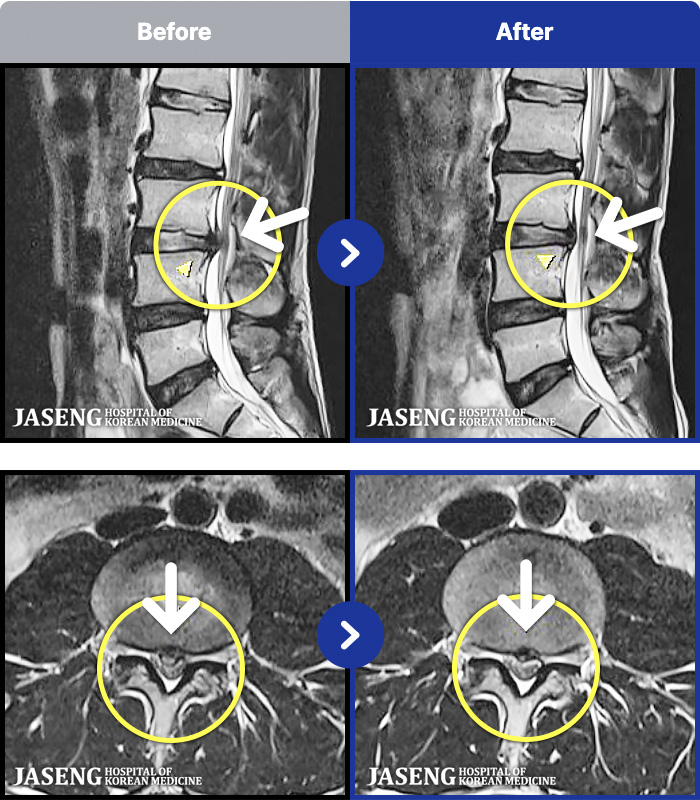

MRI ġ

1,240 MRI ũ ʸ Ȯϼ.